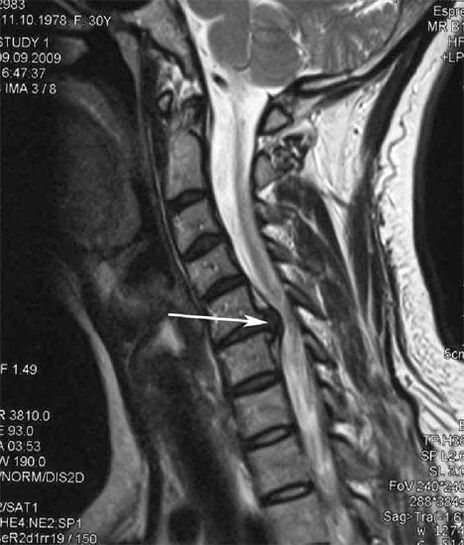

Dans les premiers stades, l'ostéochondrose est détectée par IRM.. Par la suite, la pathologie peut être diagnostiquée par radiographie. Sur les radiographies de la colonne cervicale, on note une diminution de la distance entre les vertèbres, des modifications pathologiques des facettes articulaires et une ostéophytose.

Votre cou et votre colonne vertébrale entre vos omoplates vous font constamment mal ? Cela peut être le signe du développement d'une ostéochondrose de la colonne cervicale. La pathologie est caractérisée par la destruction progressive des noyaux des disques intervertébraux avec le développement ultérieur de protubérances, de hernies, de spondylarthrose et d'arthrose cervicale.

De nombreuses personnes se plaignent de ne pas pouvoir tourner le cou en raison d'une douleur intense qui survient après avoir soudainement soulevé quelque chose de lourd. Ce phénomène indique la formation d'une hernie discale. La cause des douleurs dans le dos, le cou et les membres supérieurs est le pincement de l'une des racines nerveuses émergeant de la moelle épinière.